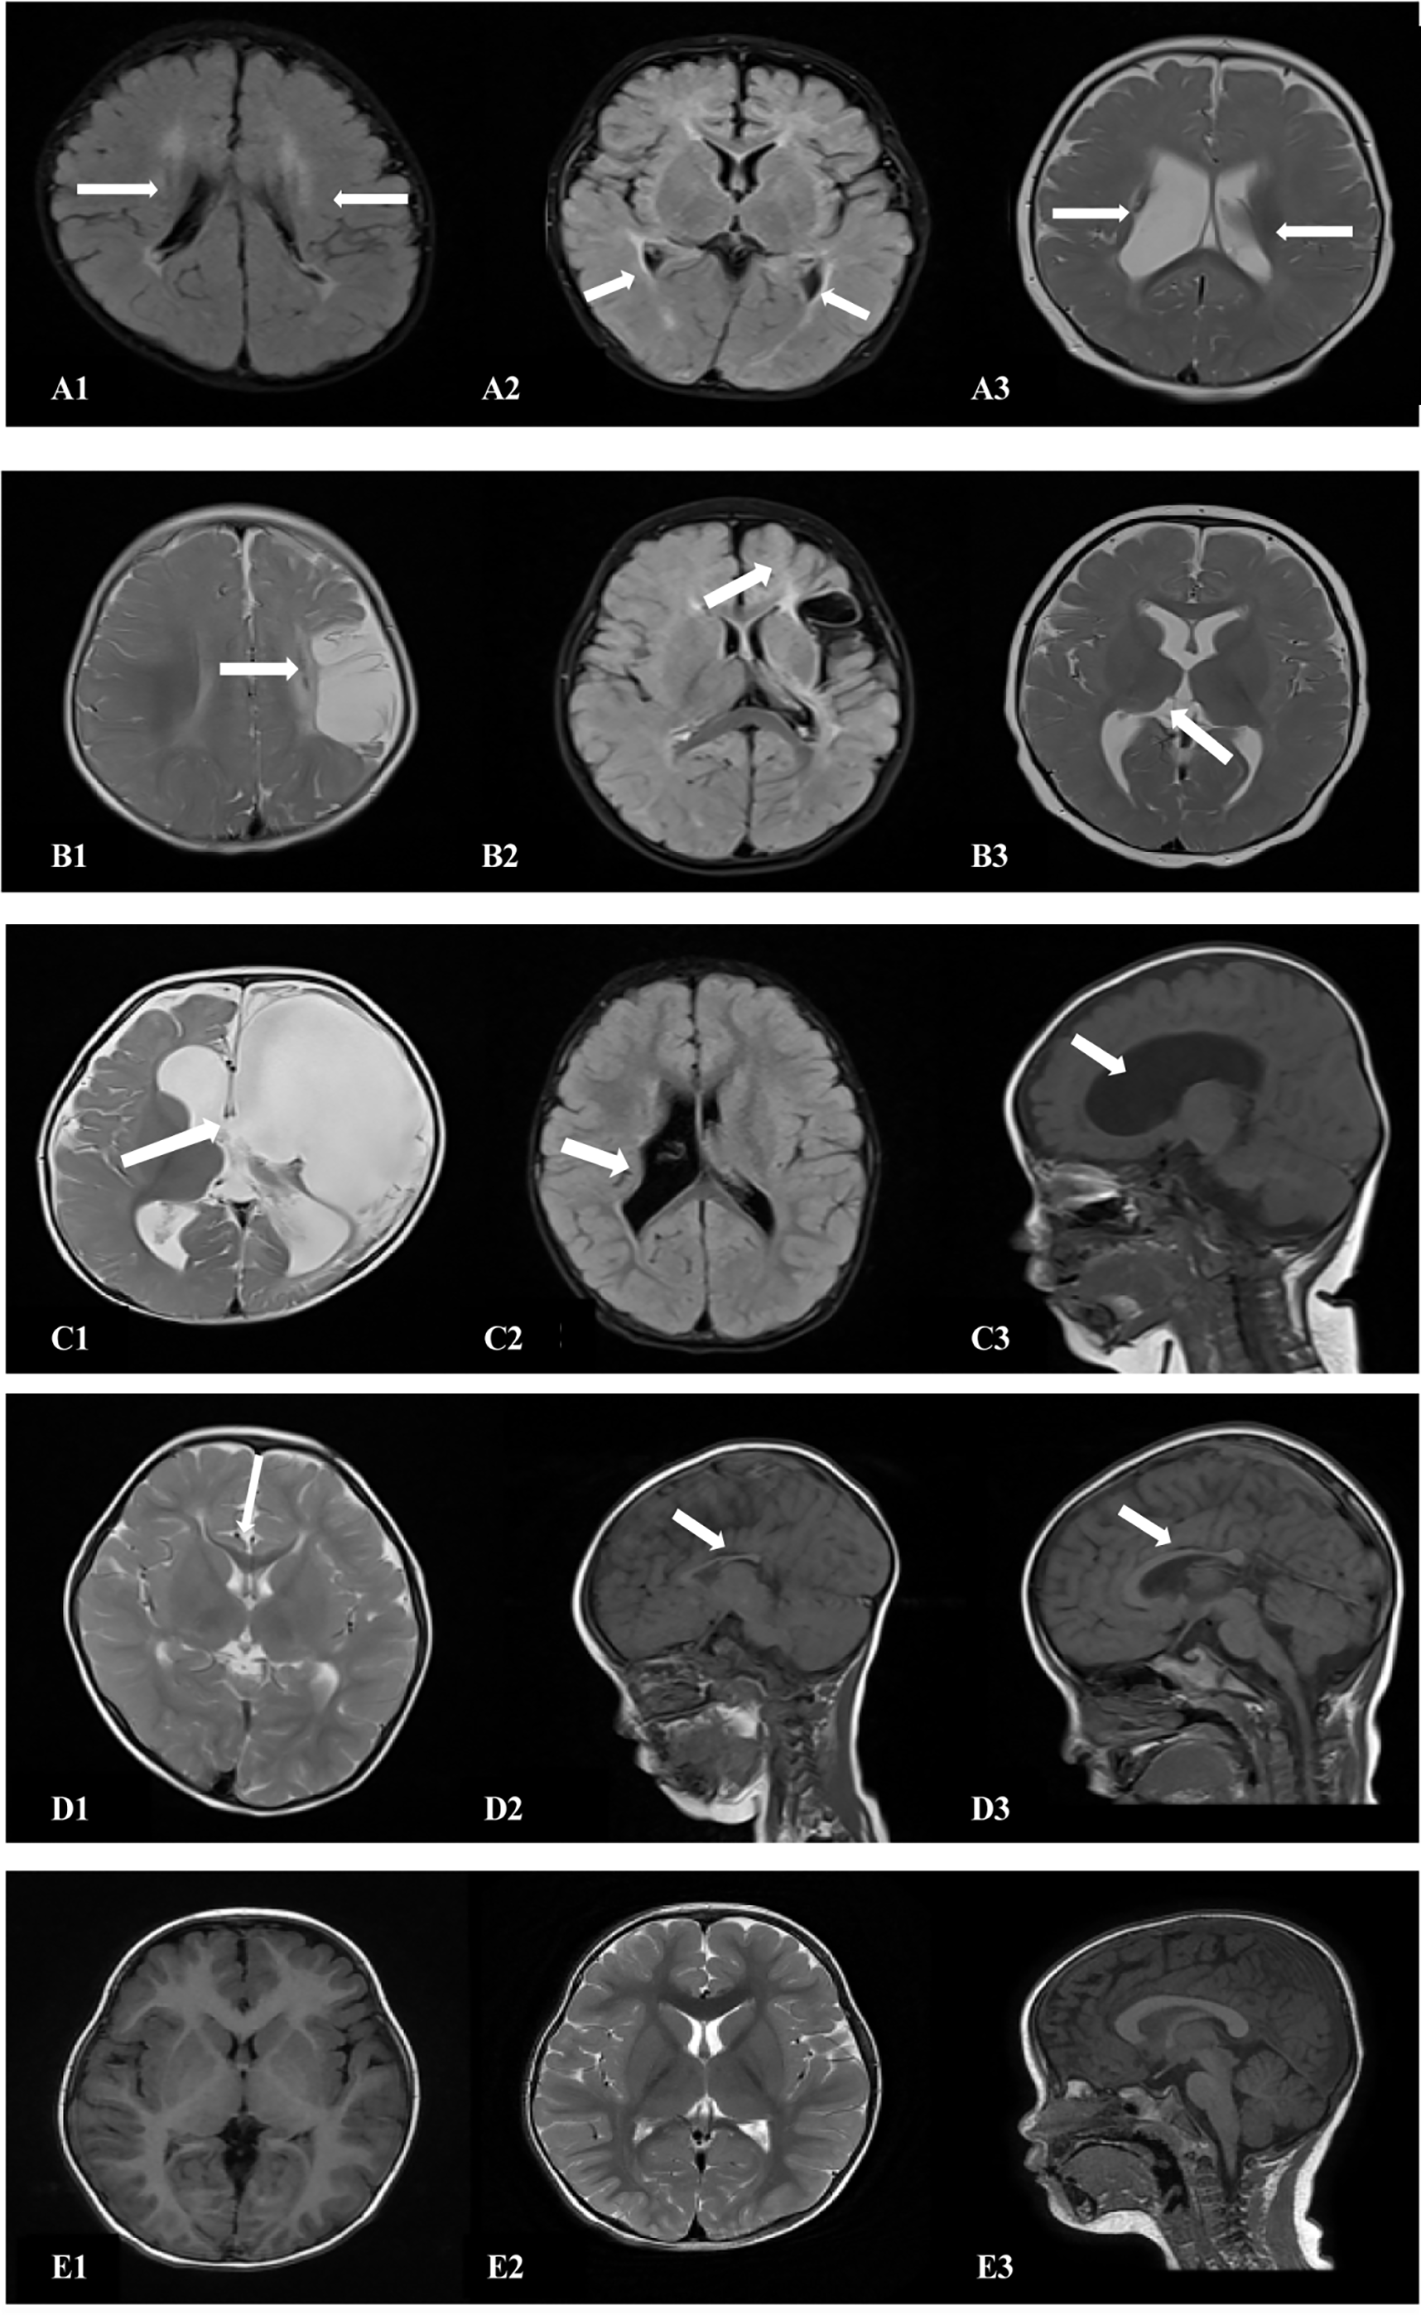

The cranial MRI findings of the 18 patients in the spastic group were as follows (Table 3): PVL was observed in 10 patients (55.6%), including three with ventriculomegaly and/or irregular shape of the lateral ventricles, four with abnormal signal foci in the ventricular white matter, and three with dysplasia of the corpus callosum. Cerebral atrophy was observed in two patients, supratentorial hydrocephalus in two patients, basal ganglia/thalamus lesions in two patients, porencephalia in one patient, and periventricular hemorrhagic infarction in one patient (Figure 4, Table 3).

Figure 4

Cranial MRI findings of the 18 patients in the ST group. (A1,2) (transverse): Irregularly shaped bilateral ventricles with nearby, irregular, patchy T1 and T2 hypersignals. (A3) (transverse section): Enlarged bilateral ventricles with nearby, patchy T2 signals. (B1) (transverse section): Left frontotemporal parietal atrophy with subcortical softening foci. (B2) (transverse section): Reduced volume of the left basal ganglia. (B3) (transverse section): Decreased volume of the left thalamus. (C1) (transverse): Left partial cerebral perforation malformation with supratentorial hydrocephalus. (C2) (transverse section): Right ventricular para-body brain penetration malformation with surrounding gliosis. (C3) (sagittal section): Supratentorial hydrocephalus. (D1) (transverse section): Thinning of the corpus callosum. (D2) (sagittal): Noticeably thinner and shorter corpus callosum. (D3) (sagittal section): Significantly shorter corpus callosum. (E1–3) (TI/T2 transverse/sagittal): Normal brain MRI.